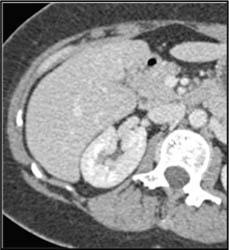

Hepatoma Invades the Inferior Vena Cava (IVC)